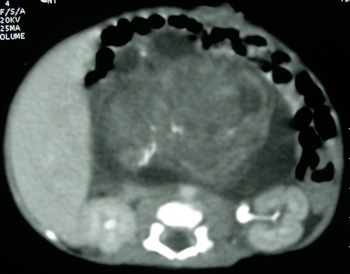

A full-term male neonate weighing 2.6 kg was referred for surgical treatment of an abdominal mass, which had been detected by an antenatal ultrasound scan (US) at 28 weeks of gestation. He was born by caesarian section, to a third gravida and second para mother. Abdominal examination revealed a firm central abdominal mass occupying almost all quadrants with restricted mobility of the mass. Plain X-ray abdomen showed the bowel gas shadows pushed to the left upper quadrant by a large space-occupying lesion. Postnatal US confirmed a large abdominal mass consisting of solid and cystic areas with foci of calcification. A computed tomographic (CT) scan of the abdomen at day five of life revealed a heterogeneous retroperitoneal mass (7cm× 5cm× 8.5cm) with calcification (Fig 1). The serum alpha-feto-protein (AFP) level was 484 ng/ml. A pan-systolic murmur was detected over the precordium. Doppler echocardiography showed a large muscular ventricular septal defect (VSD) with a left to right shunt and severe pulmonary hypertension. After consultation with the cardiologist, a decision was taken to proceed with the abdominal surgery. The child underwent laparotomy at 21 days of life. A large retroperitoneal tumor (8 cm×10cm) consisting of solid and cystic areas was found occupying mainly the right flank and central abdomen. The tumor was adherent to the surrounding structures namely the root of mesentery, superior mesenteric vessels, duodenum, colon, right kidney with renal vessels. However, there was no infiltration into any vessels or organs neither was any significant lymphadenopathy noted. Due to its friable nature, the tumor ruptured during removal resulting in intra-peritoneal spillage; however, gross complete excision of the tumor was performed (Fig. 2). Post-operatively the child developed congestive cardiac failure, which was treated with digitalis and diuretics. The child was discharged on the 10th postoperative day on full oral feeds. Histopathological sections from the tumor showed features of high-grade (grade III) immature teratoma with presence of immature neuroepithelial cells, glands, tubules, retinal tissue, hyaline cartilage and woven bone. Since the patient was a neonate and also had features of congestive cardiac failure, chemotherapy was not considered at that stage. The child underwent closure of the VSD at four months of age. At five months of age, the child presented with recurrence of the tumor, mainly on the left side of the abdomen, and a significantly elevated serum AFP level. The patient was re-operated for removal of the recurrent tumor. During surgery, a large recurrent tumor was found to be adherent to the retroperitoneal structures leading to incomplete removal and an iatrogenic duodenal injury. The child succumbed in the postoperative period to overwhelming sepsis.

Figure 1: CT scan abdomen showing a large heterogeneous retroperitoneal mass with foci of calcification. |